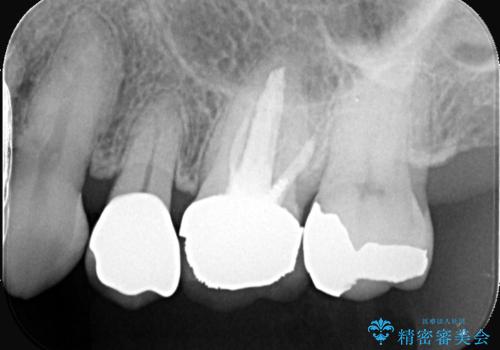

まず古い被せ物を慎重に取り除き、中に広がっていた虫歯を丁寧に除去しました。歯質の状態を確認したうえで、必要な部分には土台(コア)を補強し、セラミッククラウンを装着する準備を整えました。

最終的な被せ物には、周囲の歯と自然になじむような色合い・透明感を持つセラミックを採用。形も元の歯に近づけ、違和感のない見た目と噛み心地を再現しました。